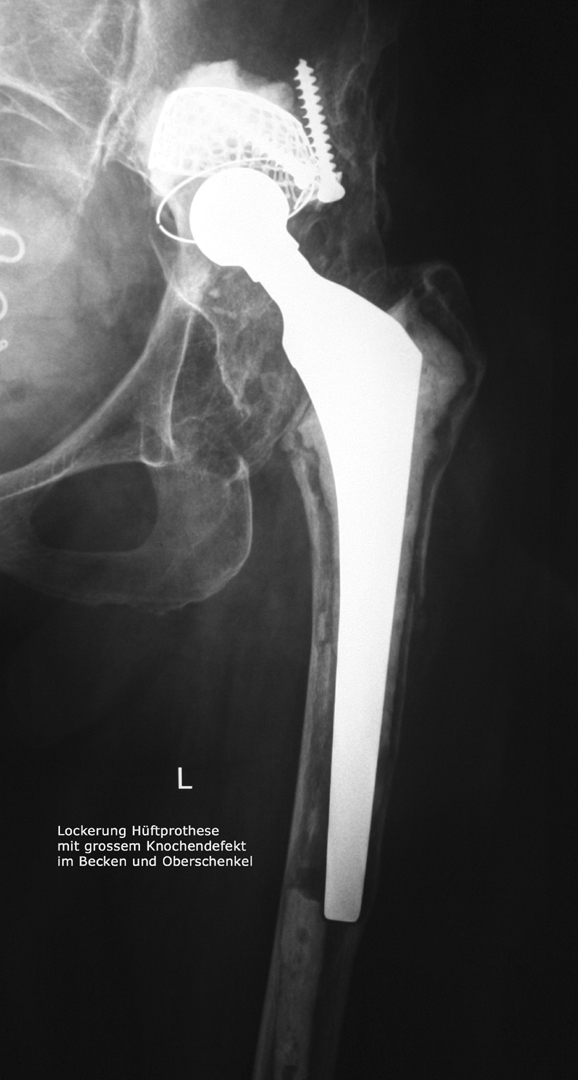

Reoperationen von gelockerten Gelenksprothesen

Reoperationen von gelockerten Gelenksprothesen sind anspruchsvolle operative Eingriffe , bei denen die Erfahrung des Operateurs und die Gabe zur richtigen Einschätzung der optimalen Versorgungsform von grosser Bedeutung ist. Reoperationen können dann erforderlich werden, wenn das Gefüge zwischen Knochen und Prothese aufgelockert wird – so kann eine Entzündung, ein vermehrter Abrieb der Prothesenteile, ein Bruch des die Prothese umgebenden Knochens aber auch Verletzungen der Weichteile eine Prothesenlockerung verursachen. Rasches Handeln ist dann angezeigt wenn der Patient über Schmerzen klagt, Röntgenuntersuchungen die Änderung der Prothesenposition

erkennen lassen oder Spezialuntersuchungen wie zum Beispiel eine Szintigraphie Hinweis auf eine Prothesenlockerung geben. Der operative Eingriff selbst ist für den Patienten belastend aber nur durch rasches Handeln kann die weitere Zerstörung von Knochen und Weichteilen verhindert werden.

Bild anklicken zum Vergrössern